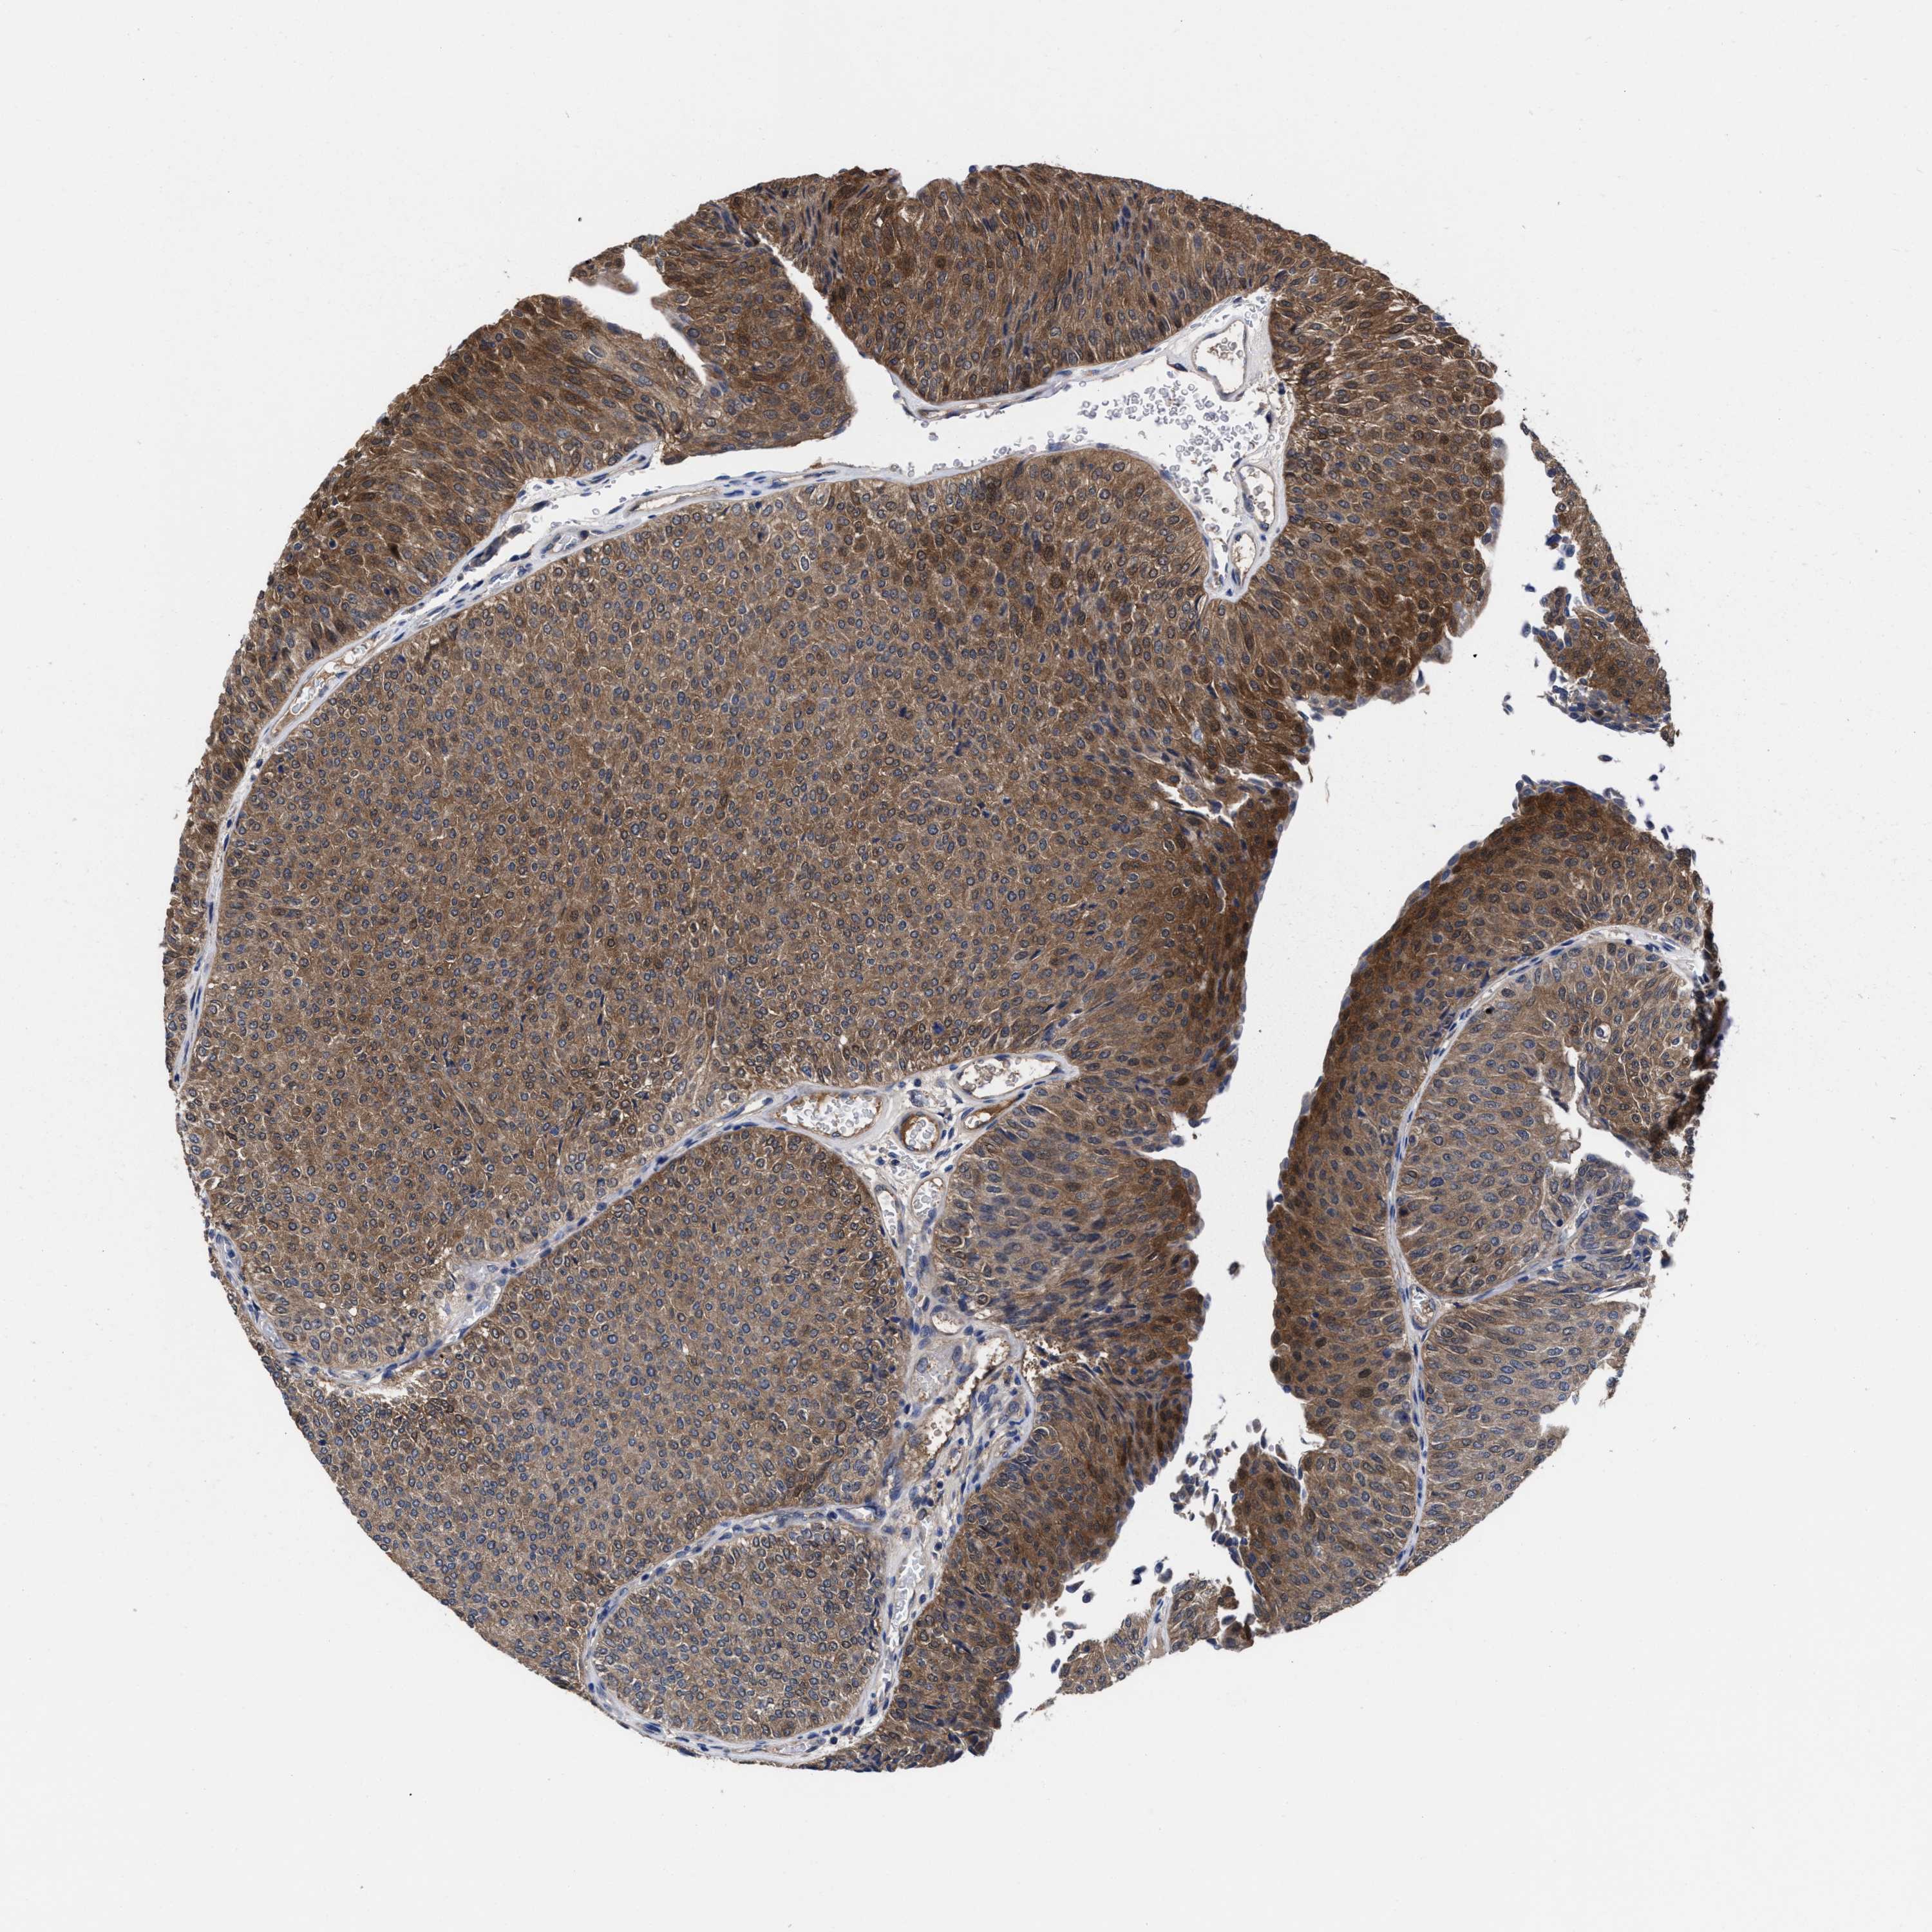

UROTHELIAL CANCER - Protein expressioni

A mouse-over function shows sample information and annotation data. Click on an image to view it in a full screen mode. Samples can be filtered based on level of antibody staining by selecting one or several of the following categories: high, medium, low and not detected. The assay and annotation is described here.

Note that samples used for immunohistochemistry by the Human Protein Atlas do not correspond to samples in the TCGA dataset.

Antibody stainingi

Antibody staining in the annotated cell types in the current human tissue is reported as not detected, low, medium, or high, based on conventional immunohistochemistry profiling in selected tissues. This score is based on the combination of the staining intensity and fraction of stained cells.

Each image is clickable and will lead to virtual microscopy that enables deeper exploration of all samples and also displays staining intensity scores, fraction scores and subcellular localization as well as patient and tissue information for each sample.

Antibody HPA022931

Staining

High

Medium

Low

Not detected

Intensity

Strong

Moderate

Weak

Negative

Quantity

>75%

75%-25%

<25%

None

Location

Nuclear

Cytoplasmic/membranous

Cytoplasmic/membranous,nuclear

Urothelial carcinoma, Low grade

Urothelial carcinoma, High grade